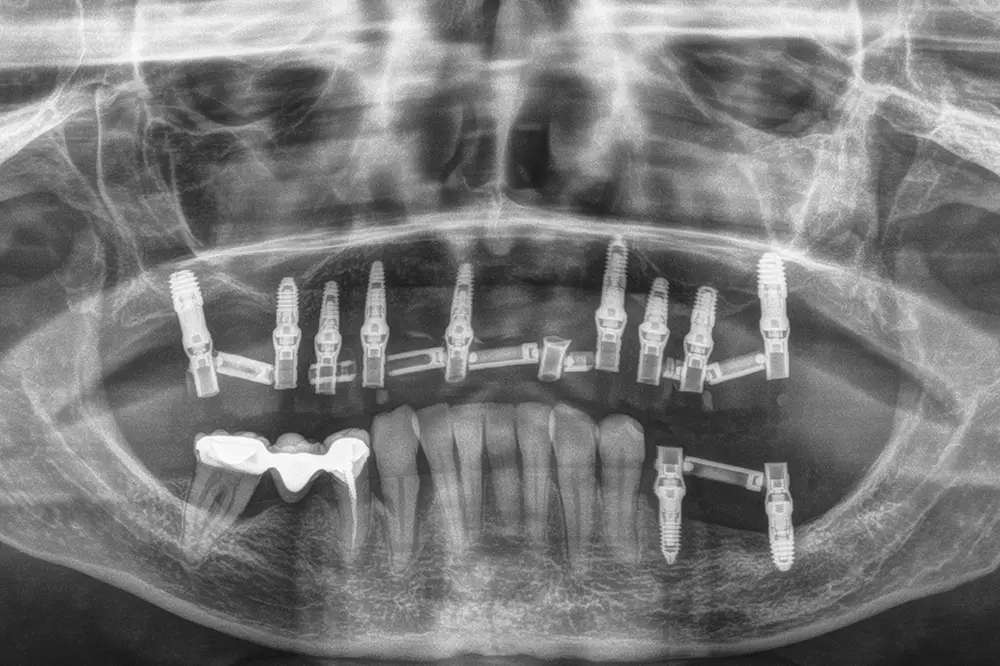

Fig. 25. Radiografía postquirúrgica tras las exodoncias y la colocación de los implantes con las diferentes técnicas comentadas anteriormente.